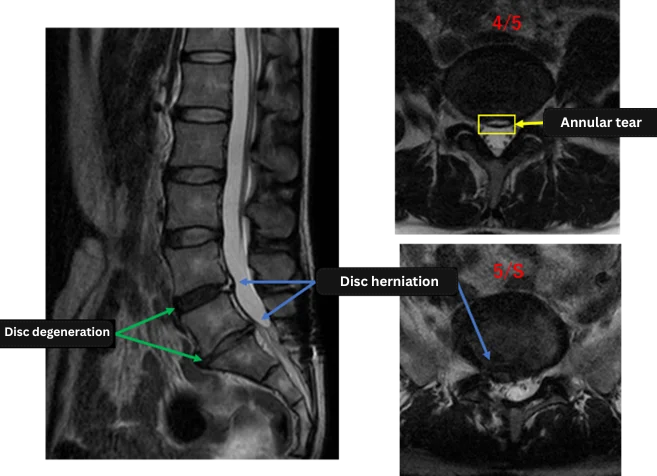

Imaging and findings

L1/2: Normal

L2/3: Normal

L3/4: Normal

L4/5: Degeneration, herniation, annular tear

L5/S: Degeneration, right herniation

The above findings were also observed on the imaging.

Degeneration, disc herniation, and annular tear were observed at L4/5 and L5/S, likely the main cause of symptoms.